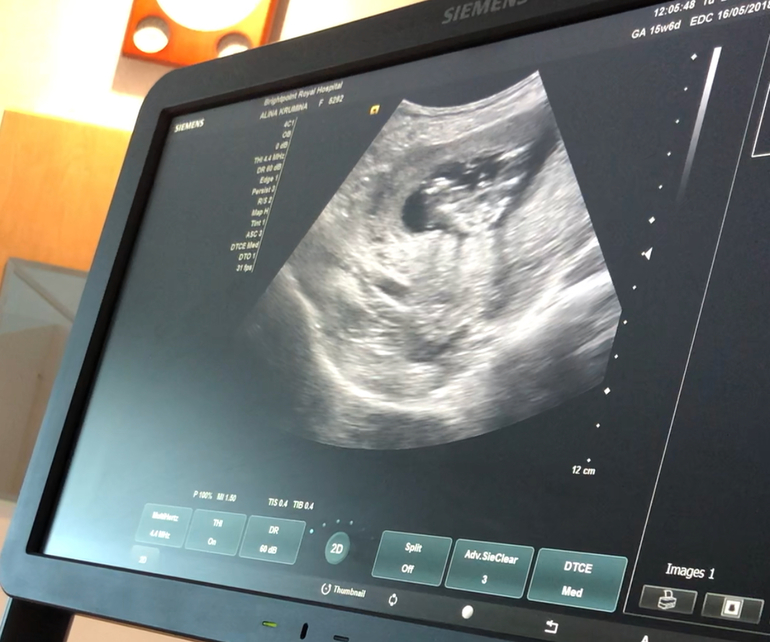

Я наконец-то дождалась результатов первого скрининга, все отлично, риски очень низкие 🙏🏻

Мой гинеколог очень удивилась, что я пришла без мужа (первый раз у нас так случилось, должны были идти вместе в воскресенье, но в итоге мне вдруг перенесли визит, а муж оказался на работе в этот день :/ ). И врач так робко спросила, хочу ли я узнать пол без мужа 🤗 Но мы уже заранее отговорили, что раз так вышло, ничего не поделаешь... Конечно не терпелось узнать кто в животике живет!

Вот мы передаём всем привет 💕💕💕💕

А тут демонстрируем кто мы 💕💕💕💕